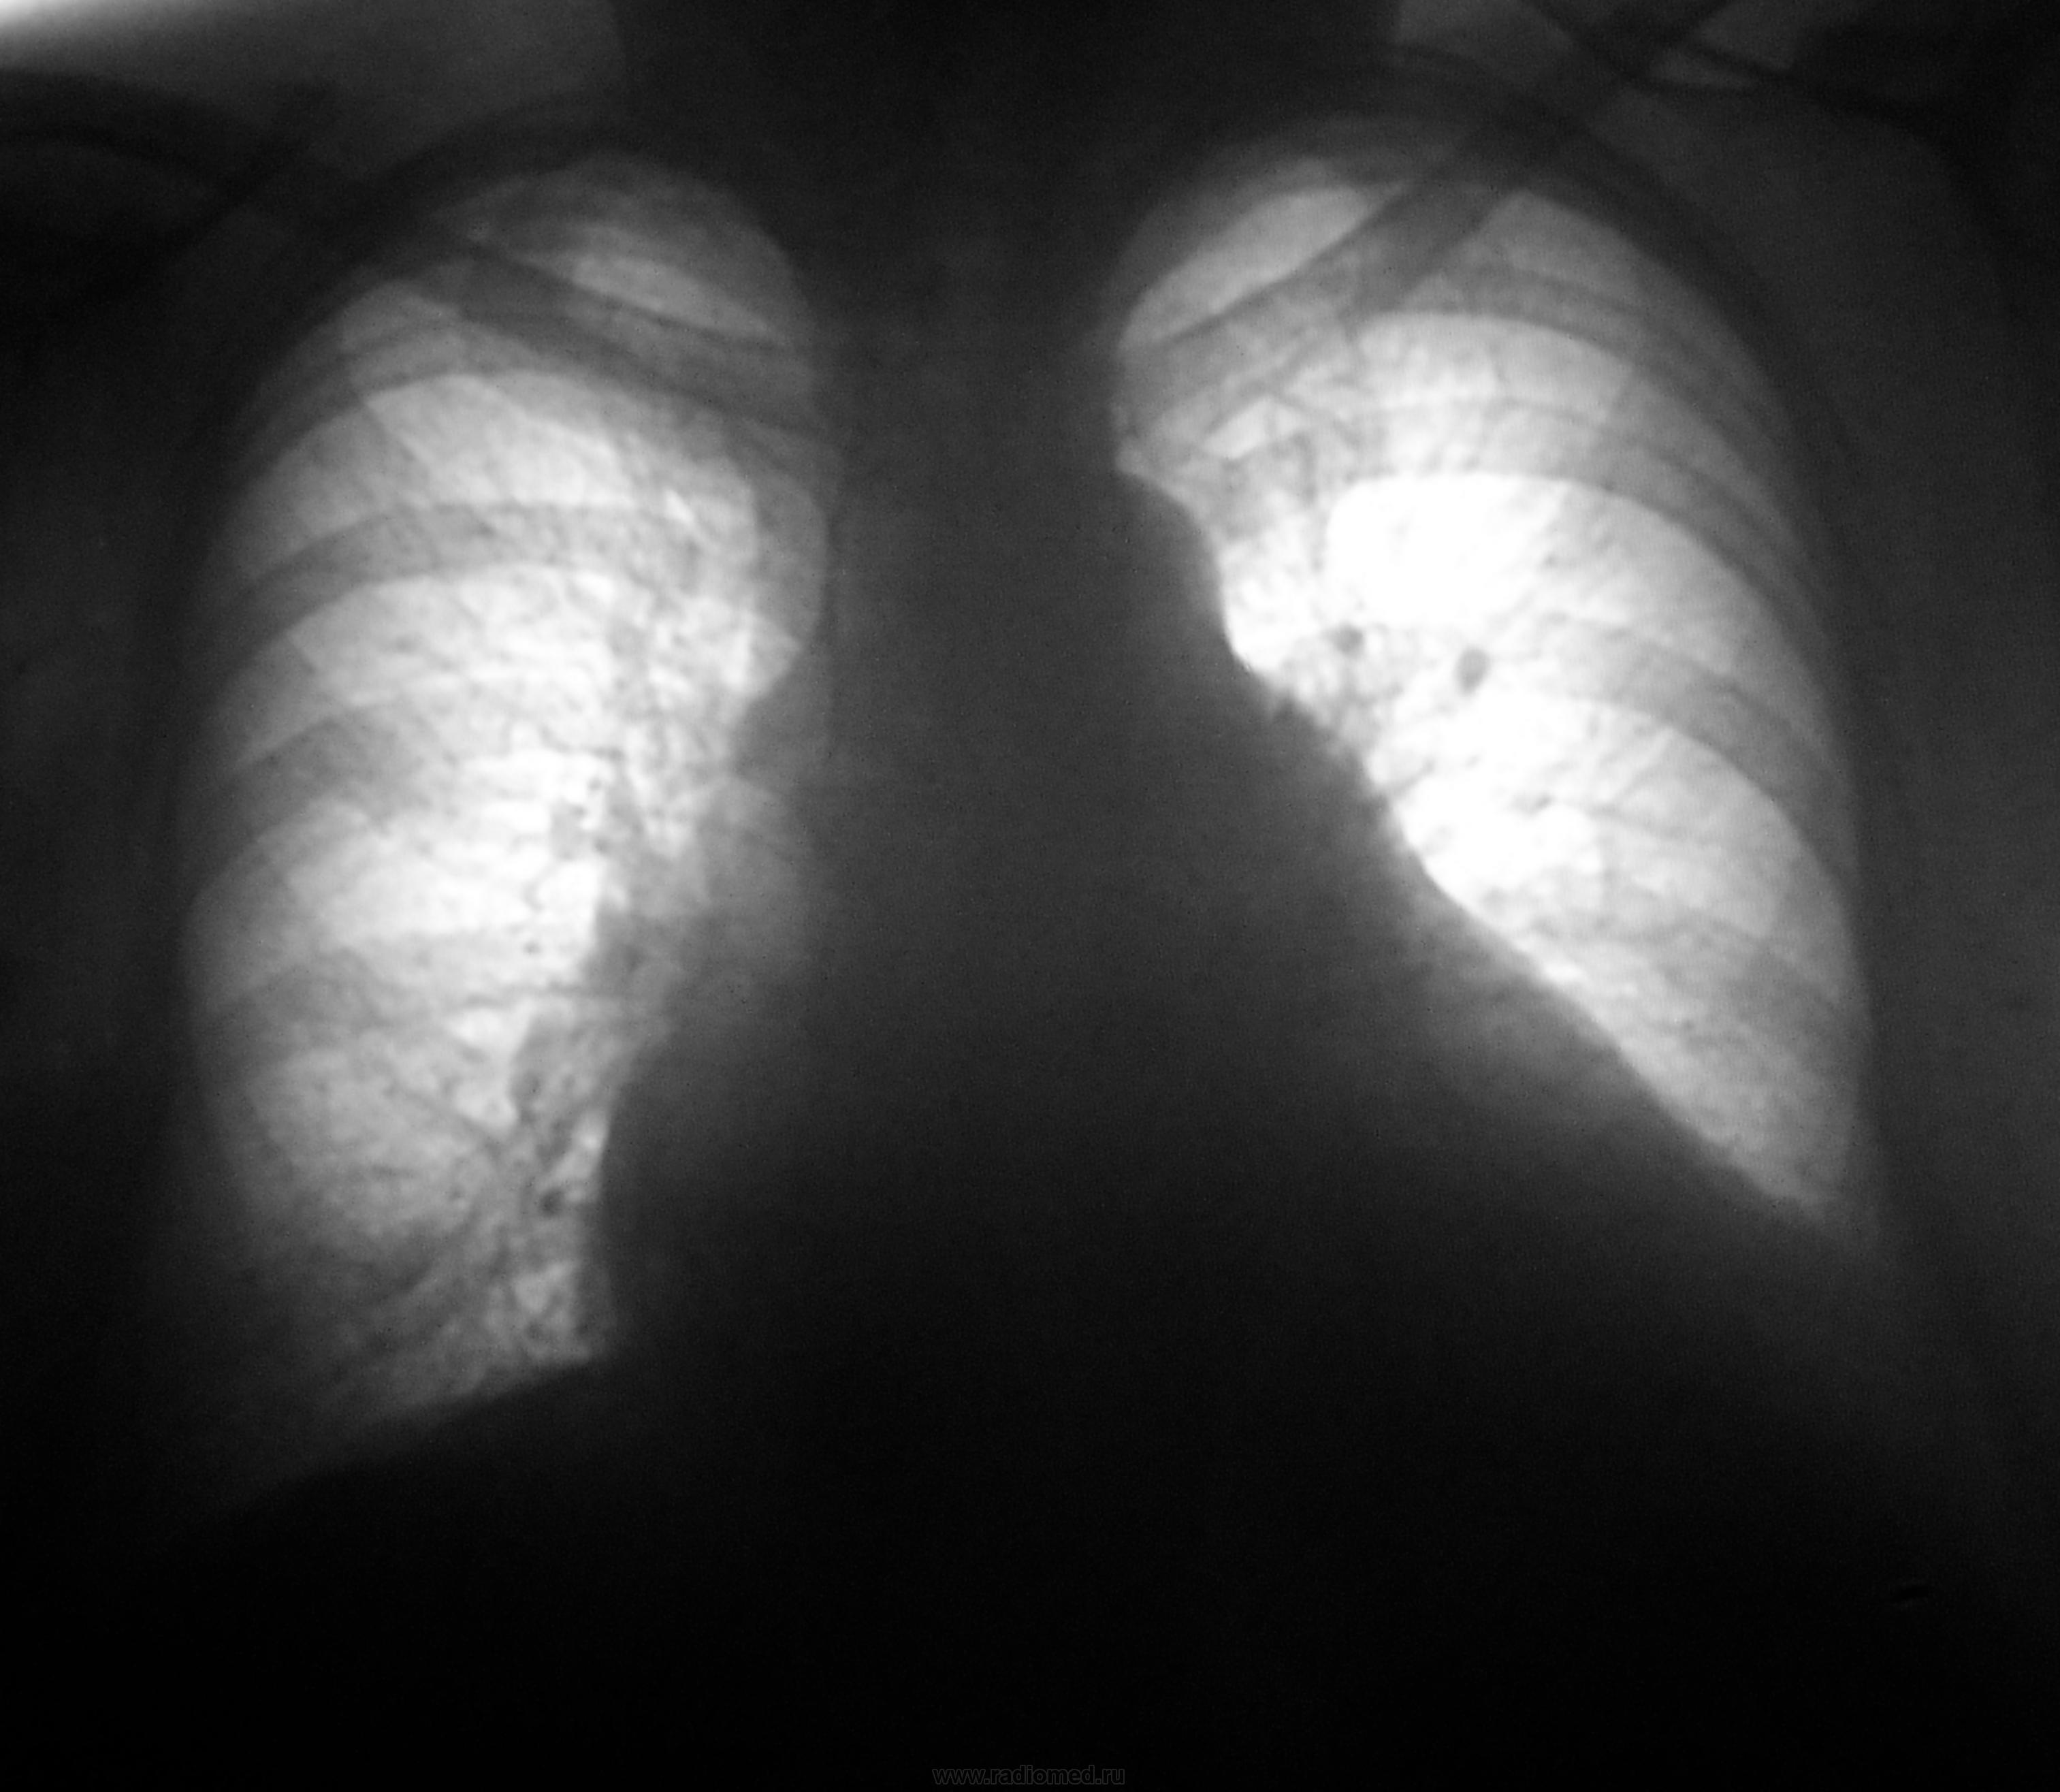

Странно что не верят заключениям, где-то не помню где читала, что множественные круглые тени с четким контуром разных размеров с тенденцией к расположению в базальных отделах практически патогномоничная рг-картина для легочных метастазов.

Какие мнения будут по флюорограмме?

Флюшка ровно через год...

Репродукции жутковатые, если флюорограммы такие же, очаги на первой легко могли быть пропущены.

Значит стопудово метастазы?

по-моему стопудово.

Вот и мне показалось, что стопудово, написал в выводах протокола - метастазы...